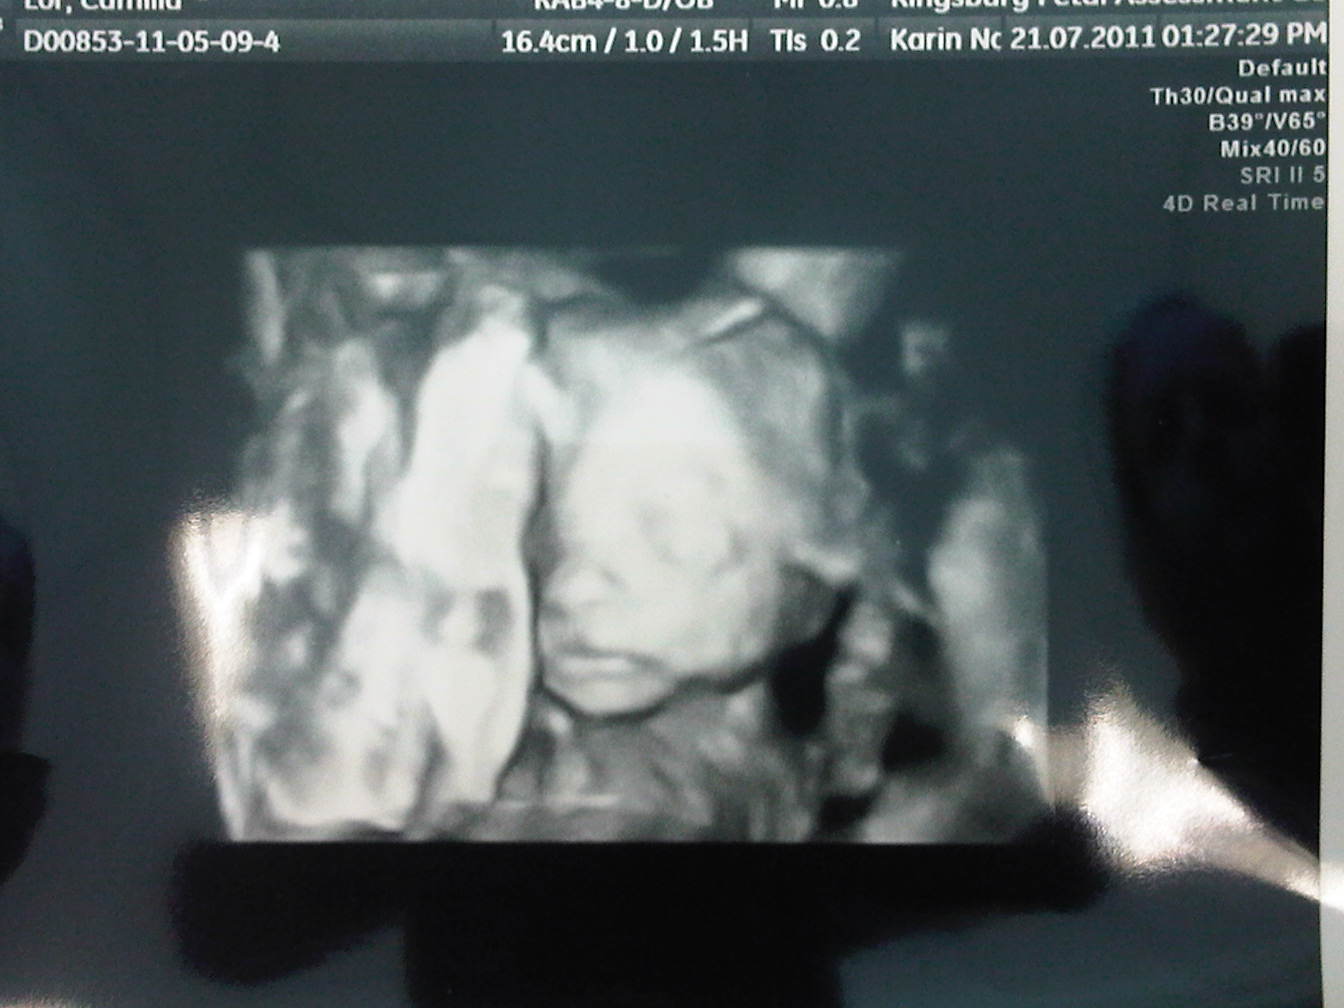

General...Just got back from the anatomy re-scan at the fetal assessment centre. The membrane is still lying on the little girl's face like a veil (she must be shy), and she has way less fluid than the little boy who is floating around in loads of space on top of her...but...she has enough and her membrane is closed! All their measurements check out fine and they are both big babies, weighing in at 629g and 693g respectively! At 23 Weeks, the average weight is 500g! Best of all, my cervix is okay and closed and measuring 29-30mm, which while it is shorter than it was a week ago (35mm) is still fine for a twin pregnancy apparently - well the sonographer said she was happy with it. The usual length of a cervix should be 40mm, and if it drops below 30mm, then could be sign of preterm labour risk. So no more shortening okay dear cervix!!!! And as a special suprise, we got a 4D scan pic of our "big" boy, but not of our girl as she was not cooperating at all lying with her face towards my spine and her back to us...hopefully she has moved in time for the 4D scan I just booked!

Here is our gorgeous boy...how cute is this little tot?